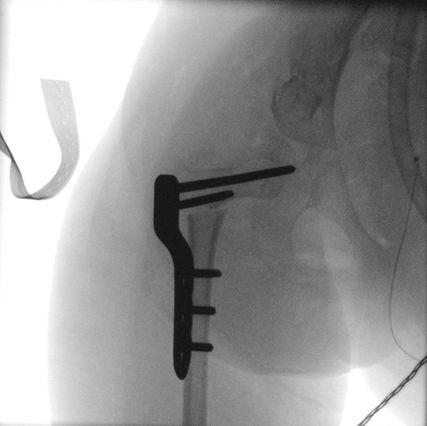

Abb. 1: Hüftrekonstruktion mit VDRO, Dega-Beckenosteotomie und medialer Hemiepiphysiodese durch die Positionierung einer langen Schraube in den kaudalen Anteil der Femurepiphyse

In rezenten Studien wurde ein wachstumslenkender Eingriff an der Hüfte propagiert, der insbesondere bei Kindern mit erhöhtem Operationsrisiko eine mögliche Therapiealternative zu einer deutlich invasiveren Hüftrekonstruktion darstellt. Es wird hierbei im Rahmen einer minimal invasiven Operation eine Schraube perkutan in den medialen Anteil der Wachstumsfuge eingebracht. Durch die temporäre Hemmung der Wachstumsfuge kommt es zu einer graduellen Varisierung mit Senkung des erhöhten CCD-Winkels und einer konsekutiven Abnahme des Reimers-Index.

Empfohlen wird diese Methode für Kinder im Alter von 4–10 Jahren mit einem Reimers-Index von 30–50%.6 Ab einem Reimers-Index von 50% ist ein rekonstruktiver Eingriff mit Femur- und Beckenosteotomie indiziert.

Durch die Hemiepiphysiodese lässt sich das Wachstum des proximalen Femurs effektiv beeinflussen und auf diese Weise kann der Migration der betroffenen Hüfte entgegengewirkt werden. Allerdings müssen die eingebrachten Schrauben bei knapp einem Drittel der betroffenen Kinder (27%) gewechselt werden und es sind sorgfältige radiologische und klinische Nachkontrollen erforderlich.7

Von einzelnen Autoren wurde darüber hinaus die Möglichkeit einer permanenten medialen Hemiepiphysiodese mittels Bohrer und Curette beschrieben, welche im Rahmen der Metallentfernung nach einer Femurosteotomie zur Rezidivprophylaxe durchgeführt werden kann. Das Ziel ist auch hier, durch eine Wachstumslenkung eine Revalgisierung der Hüfte und damit eine neuerliche Luxation zu verhindern.6